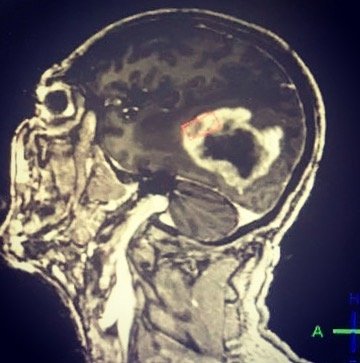

Cirugía tumores cerebrales